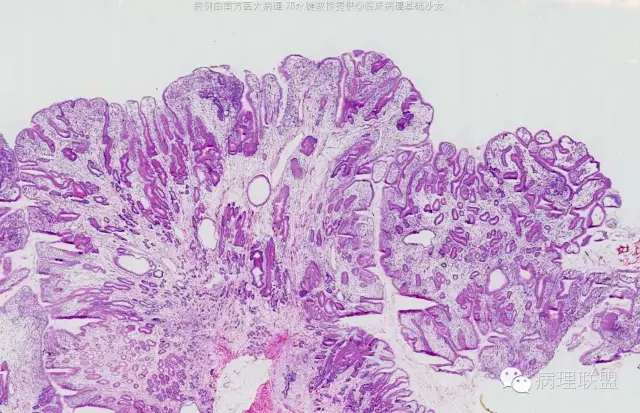

男,58岁,胃窦2.5×2.1×1.5cm大小肿物。冰冻切片。(病例由南方医科大学 邓永键教授提供,致谢!)

平滑肌束进入病变中,重点是表面腺体与正常腺体类似。

错构瘤性息肉/Peutz-Jephers息肉,在胃体,表面腺体是胃体腺,胃窦部是粘液腺;在小肠、大肠,表面腺腺体是小肠腺、大肠腺。该病变可以从食管至肛门都可发生。如果不出现出血、溃疡、梗阻症状,不体检,病人不会出现症状,不易被发现。小肠发生,易致肠梗阻、肠扭转。肛门发生,可脱出似内痔。